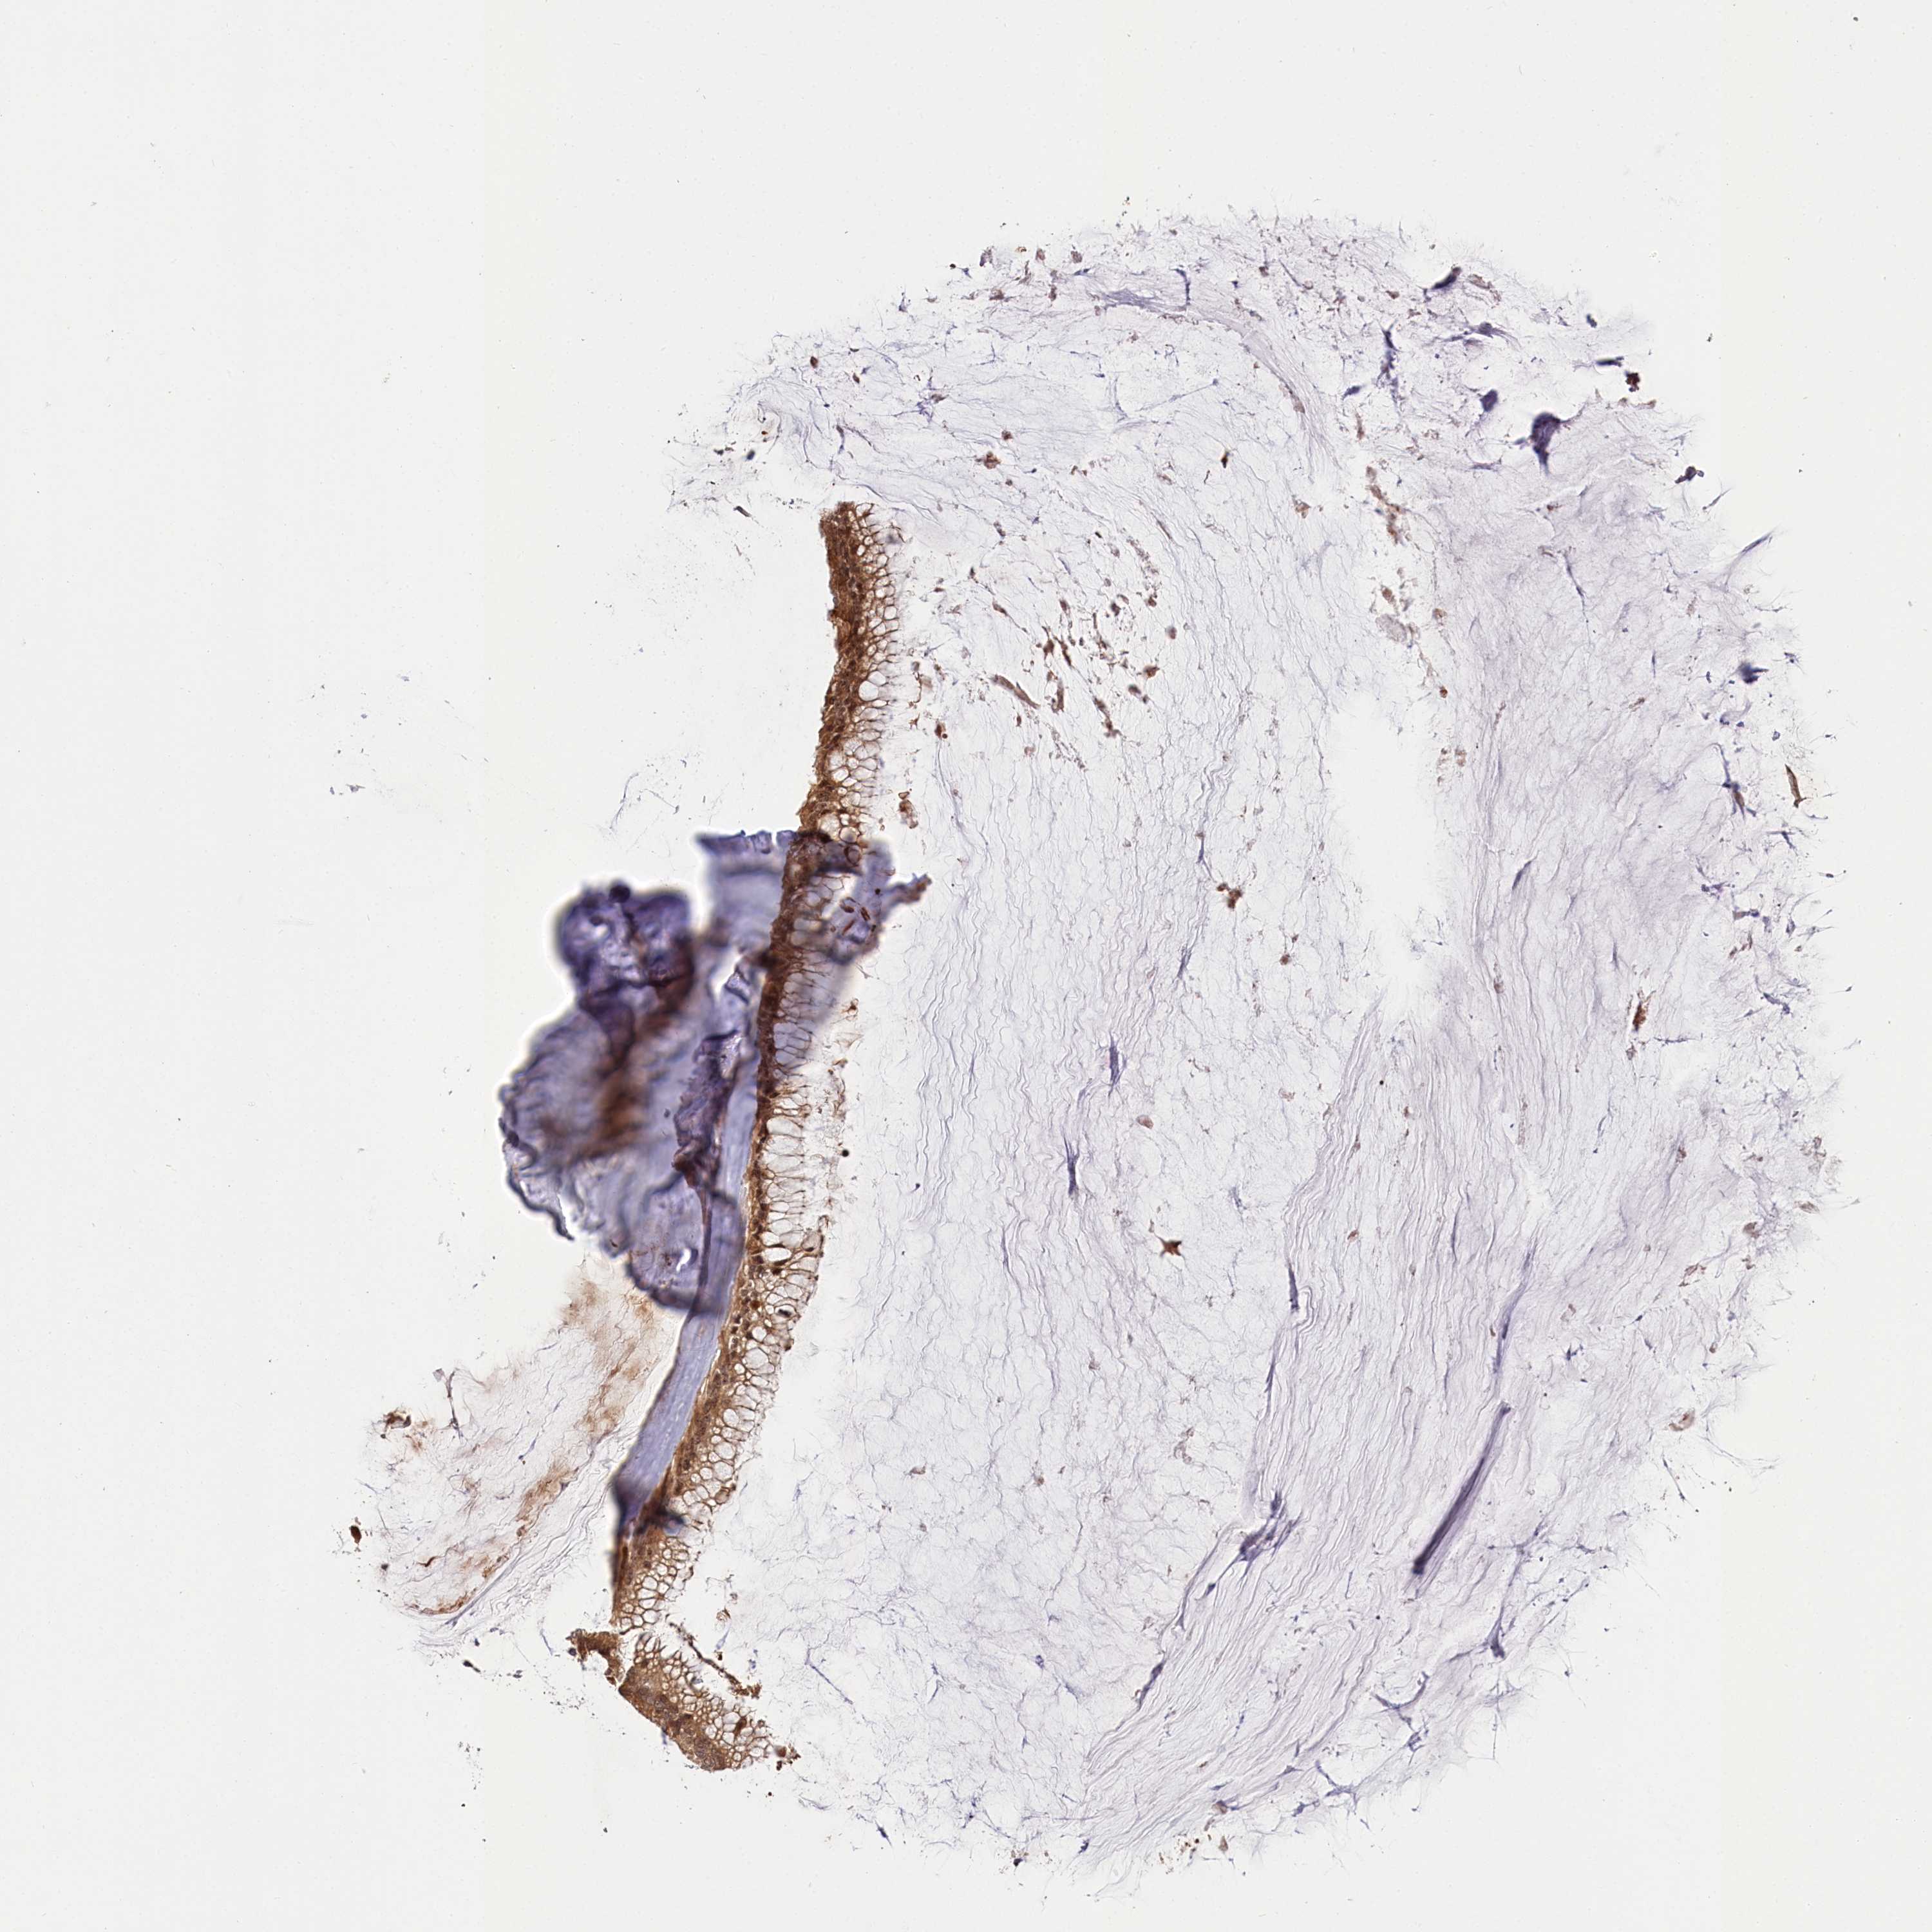

OVARIAN CANCER - Protein expressioni

A mouse-over function shows sample information and annotation data. Click on an image to view it in a full screen mode. Samples can be filtered based on level of antibody staining by selecting one or several of the following categories: high, medium, low and not detected. The assay and annotation is described here.

Note that samples used for immunohistochemistry by the Human Protein Atlas do not correspond to samples in the TCGA dataset.

Antibody stainingi

Antibody staining in the annotated cell types in the current human tissue is reported as not detected, low, medium, or high, based on conventional immunohistochemistry profiling in selected tissues. This score is based on the combination of the staining intensity and fraction of stained cells.

Each image is clickable and will lead to virtual microscopy that enables deeper exploration of all samples and also displays staining intensity scores, fraction scores and subcellular localization as well as patient and tissue information for each sample.

Antibody HPA037811

Antibody HPA037812

Cystadenocarcinoma, serous, NOS